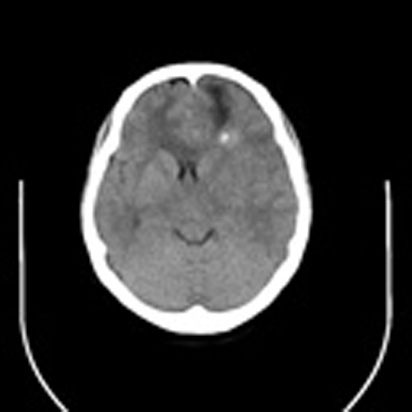

标题: CT16829:女,36,近20天偶有口眼歪斜短暂发作史,近日头痛。 [打印本页]

标题: CT16829:女,36,近20天偶有口眼歪斜短暂发作史,近日头痛。

近20天偶有口眼歪斜短暂发作史,近日头痛。患者先做ct发现病变后又做了mri检查,前日上传2次ct图像均未成功,今日补上。

大脑中线部位肿瘤向两侧生长,可见明显钙化影,考虑少枝胶质瘤,建议增强除外脑膜瘤

左额混杂密度肿块,经胼胝体跨越中线向右额叶生长,多考虑少支胶质细胞瘤,建议mr增强扫描,待排除血管畸形。